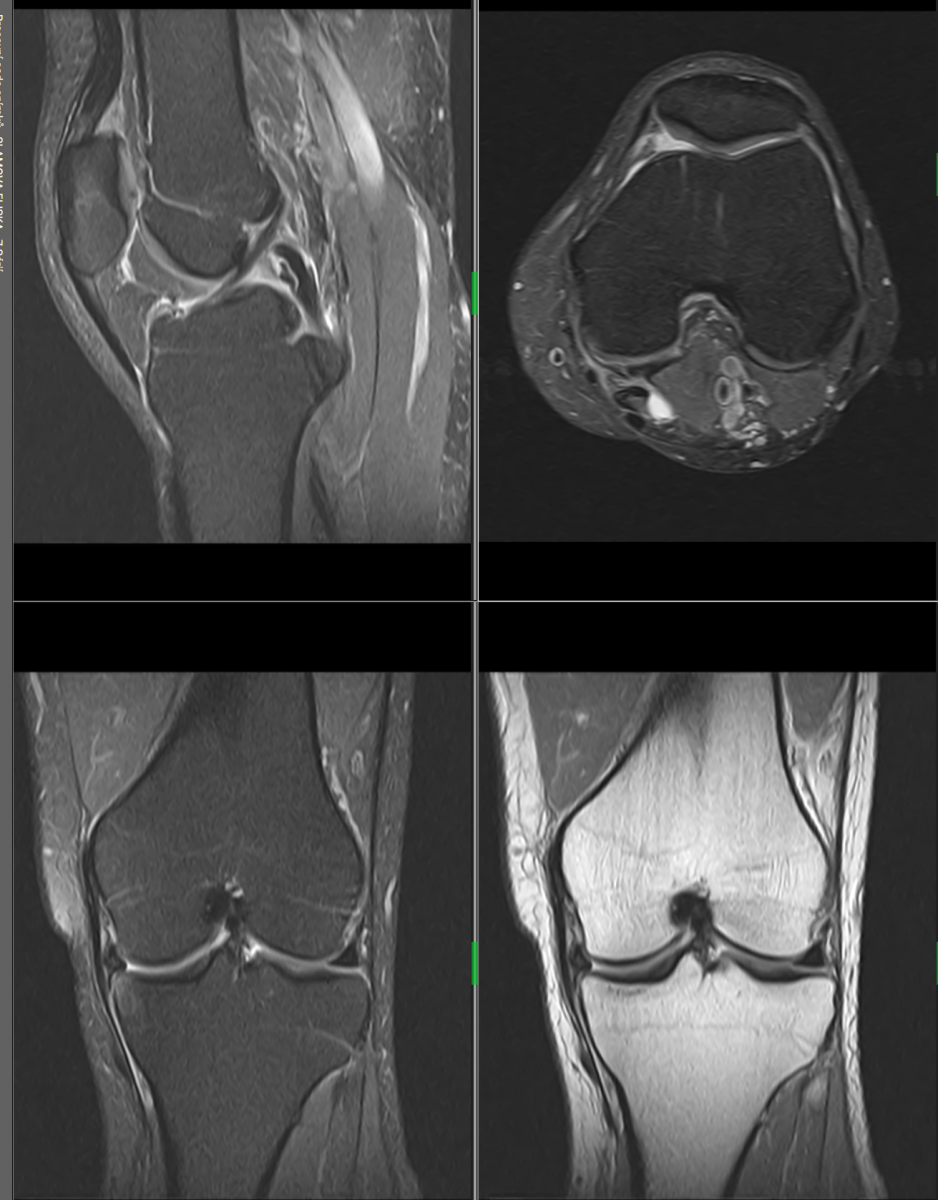

MR muskuloskeletálního systému

Vyšetření ramenního, kolenního, kyčelního, hlezenního kloubu, temporomandibulární (čelistní klouby), MR je suverénní při vyšetření menisků, vazů, chrupavek, svalů,MR dokonce zobrazí zlomeniny, které nejsou viditelné při běžném rentgenovém vyšetření nebo na CT (což je umožněno zejména identifikací edému), průkaz infekcí kostní tkáně (osteomyelitida) a nádorů (metastázy do kostí a kloubů).